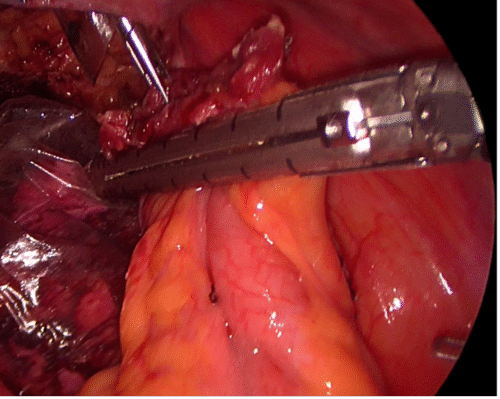

Asegurada la isquemia, resecamos la lesión con técnica de enucleación con tijera fría en la mano diestra y el aspirador (idealmente de trompeta) que permite presentarnos el sitio de sección y aspirar para obtener una visión completa durante todo el procedimiento. El segundo ayudante, con una pinza de 5 mm ubicada en el flanco, puede facilitar la presentación del tumor. Durante la disección si nos encontramos con un vaso mayor o vía urinaria, la controlamos con clips de titanio y seccionamos sobre estos para evitar perder tiempo en repararlos posteriormente. Esta técnica puede ser un poco más lenta que seccionar sobre tejido sano alejado del tumor, pero, preservamos mayor cantidad de tejido renal y se facilita la reparación sin sacrificar el resultado oncológico. En nuestra serie tenemos sólo tres recidivas locales en más de 250 casos (1,2%) (Figura 27).

Antes de tener el dato de estas tres recidivas, liberábamos la pieza quirúrgica, abandonándola en el abdomen y comenzábamos rápidamente la reparación del defecto quirúrgico para no aumentar el tiempo de isquemia por pinzamiento. Actualmente antes de completar la resección, dejamos la pieza fijada al lecho por unos milímetros de tejido y la atrapamos en una bolsa de PVC de 10 cm. Ahora entonces, la abandonamos en el abdomen aislada en su bolsa, evitando una posible contaminación local. De rutina tomábamos varias muestras del lecho renal con una pinza saca bocado (biótomo) para un informe histológico contemporáneo. Con tantos casos realizados y siempre con biopsias negativas, no hacemos, en la actualidad, biopsia contemporánea y de paso disminuimos los costos de la cirugía. Frecuentemente electrodesecamos la superficie del lecho con energía monopolar a 100 W de potencia en modo spray(36). Rellenamos el defecto quirúrgico con un rollo de celulosa oxidada (Surgicel®), aplicamos una matriz hemostática con trombina sintética (Surgiflo®) en el fondo con una sonda de alimentación 10F y usamos una sutura hemostática con puntos separados de poliglactina 910 (Vicryl®) tensionados y asegurados con clip de ligadura de polímero (Hem-o-LockTM) en sus extremos sin cambiar las líneas de fuerza y evitamos rebanar el parénquima. Liberamos la pinza arterial y comprobamos la ausencia de sangrado (26,35). Esta reparación difiere a la que realizan muchos grupos y creemos que nuestra técnica produce un menor daño en el tejido renal que queremos preservar(37). Lo primero es que durante la resección controlamos en forma contemporánea vasos mayores y estructuras de la vía urinaria con clips de titanio, antes de seccionarlos. Otros grupos utilizan de rutina puntos en el lecho tumoral para contener el sangrado y reparar una vía urinaria inadvertidamente abierta. Con estos puntos “ciegos” se podrían incluir inadvertidamente arteriolas y venas provocando una mayor isquemia y/o favoreciendo la creación de una fístula arterio-venosa. Los puntos hemostáticos que utilizamos no se profundizan más allá de la corteza renal en donde no comprometemos la integridad de arteriolas ni vía urinaria(26,37) (Figura 28).

Realizamos aseo de la cavidad abdominal, si es necesario, con abundante agua bidestilada. Reponemos el riñón en la bolsa de Gerota, suturándola con un punto continuo de material reabsorbible. Se extirpa la bolsa con la lesión integra por un sitio de punción, si el tamaño lo permite o por el sitio de Nyhus. Se completa el procedimiento verificando la ausencia de sangrado en los sitios de punción, común a todas las cirugías. En resumen, nuestra técnica de nefrectomía parcial contempla: resección del tumor por enucleación y reparación de estructuras vasculares o vía urinaria con clips en la superficie del lecho tumoral que no comprometen otras estructuras profundas. La reparación del defecto quirúrgico con puntos superficiales separados de material absorbible sobre un rollo de celulosa oxidada. Con esto necesitamos menor tensión y provocamos menor daño isquémico (técnica de reparación superficial) (Figura 28).